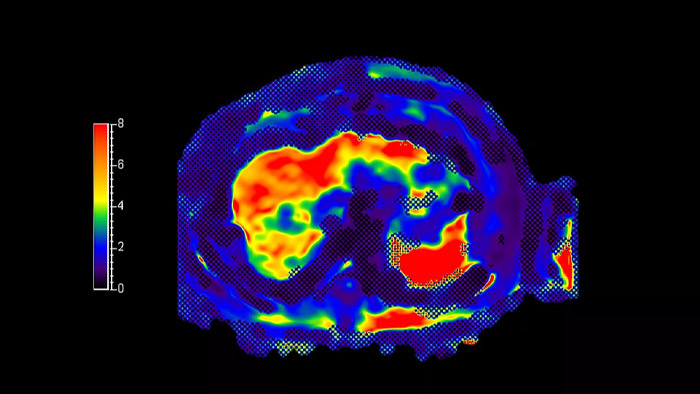

MR Elastography extension

Co-Creation Facility Cincinnati Children’s Hospital, USA